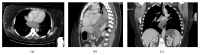

Neoadjuvant imatinib for gastrointestinal stromal tumours (GISTs) is increasingly used nowadays. As oesophagectomy is associated with high morbidity and mortality, a preoperative downsizing of an oesophageal GIST to limit the extent of resection would be ideal. Because these tumours are rare and neoadjuvant treatment with imatinib is recent, there is limited literature available regarding neoadjuvant administration of imatinib in patients with oesophageal GISTs. A 50-year-old woman presented with total dysphagia. An upper endoscopy and biopsy revealed a large submucosal KIT-positive GIST obstructing the mid oesophagus. CT confirmed a lesion measuring 99 mm × 50 mm × 104 mm. Because the size and location of the tumour increased the risk of intraoperative rupture, it was decided to administer preoperative imatinib. The patient had an excellent clinical and radiological response. Her dysphagia gradually resolved and the follow-up CT scans of the first 10 months showed a gradually reducing tumour size to 54 mm × 33 mm × 42 mm. The patient underwent an uneventful laparoscopic-assisted Ivor-Lewis oesophagectomy. Postoperatively, the patient continued with adjuvant imatinib. At the last follow-up, 1 year from operation and 38 months from the diagnosis, the patient is disease free.